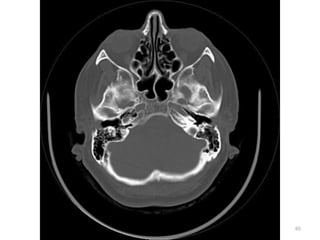

IMAGENS ÓSSEAS

83

1. GLOBO OULAR (VITRIO)

2. FORAME MAGNUM

3. MUSCULO PITERIGÓIDE

MEDIAL

4. SEIO ESFENOIDAL

5. SEIO MAXILAR

6. ORELHA

1

2

3

4

5

6

ANATOMIA

1. HEMISFÉRIO OCCIPTAL D

2. LOBO TEMPORAL D

3. NERVO ÓPTICO E

4. CÉLULAS MASTÓIDEAS E

5. SEIO FRONTAL

88

1. CORPO CALOSO

2. CORNO ANTERIOR

DO VENTRÍCULO

LATERAL D

3. FISSURA DE SILVYUS 4. NÚCLEO

LENTICULADO

5. TERCEIRO

VENTRÍCULO

6. SEIO SAGITAL SUPERIOR

4 5

Tomography class